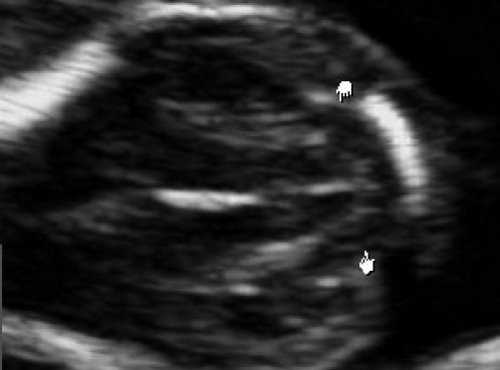

В аксиальном срезе головки определяется мозжечок (обведен пунктиром) огибающий ножки мозга, изогнутый, в виде "банана";. К сведению мозжечок определяется с 12 нед беременности. Стрелкой указано то, что отсутствует расстояние между мозжечком и затылочной костью, т.е. отсутствует большая цистерна.

Рис. 6. Проявление синдрома Арнольда-Киари - смещение мозжечка, признак "банана" у плода со spina bifida, беременность 12,4 недель.